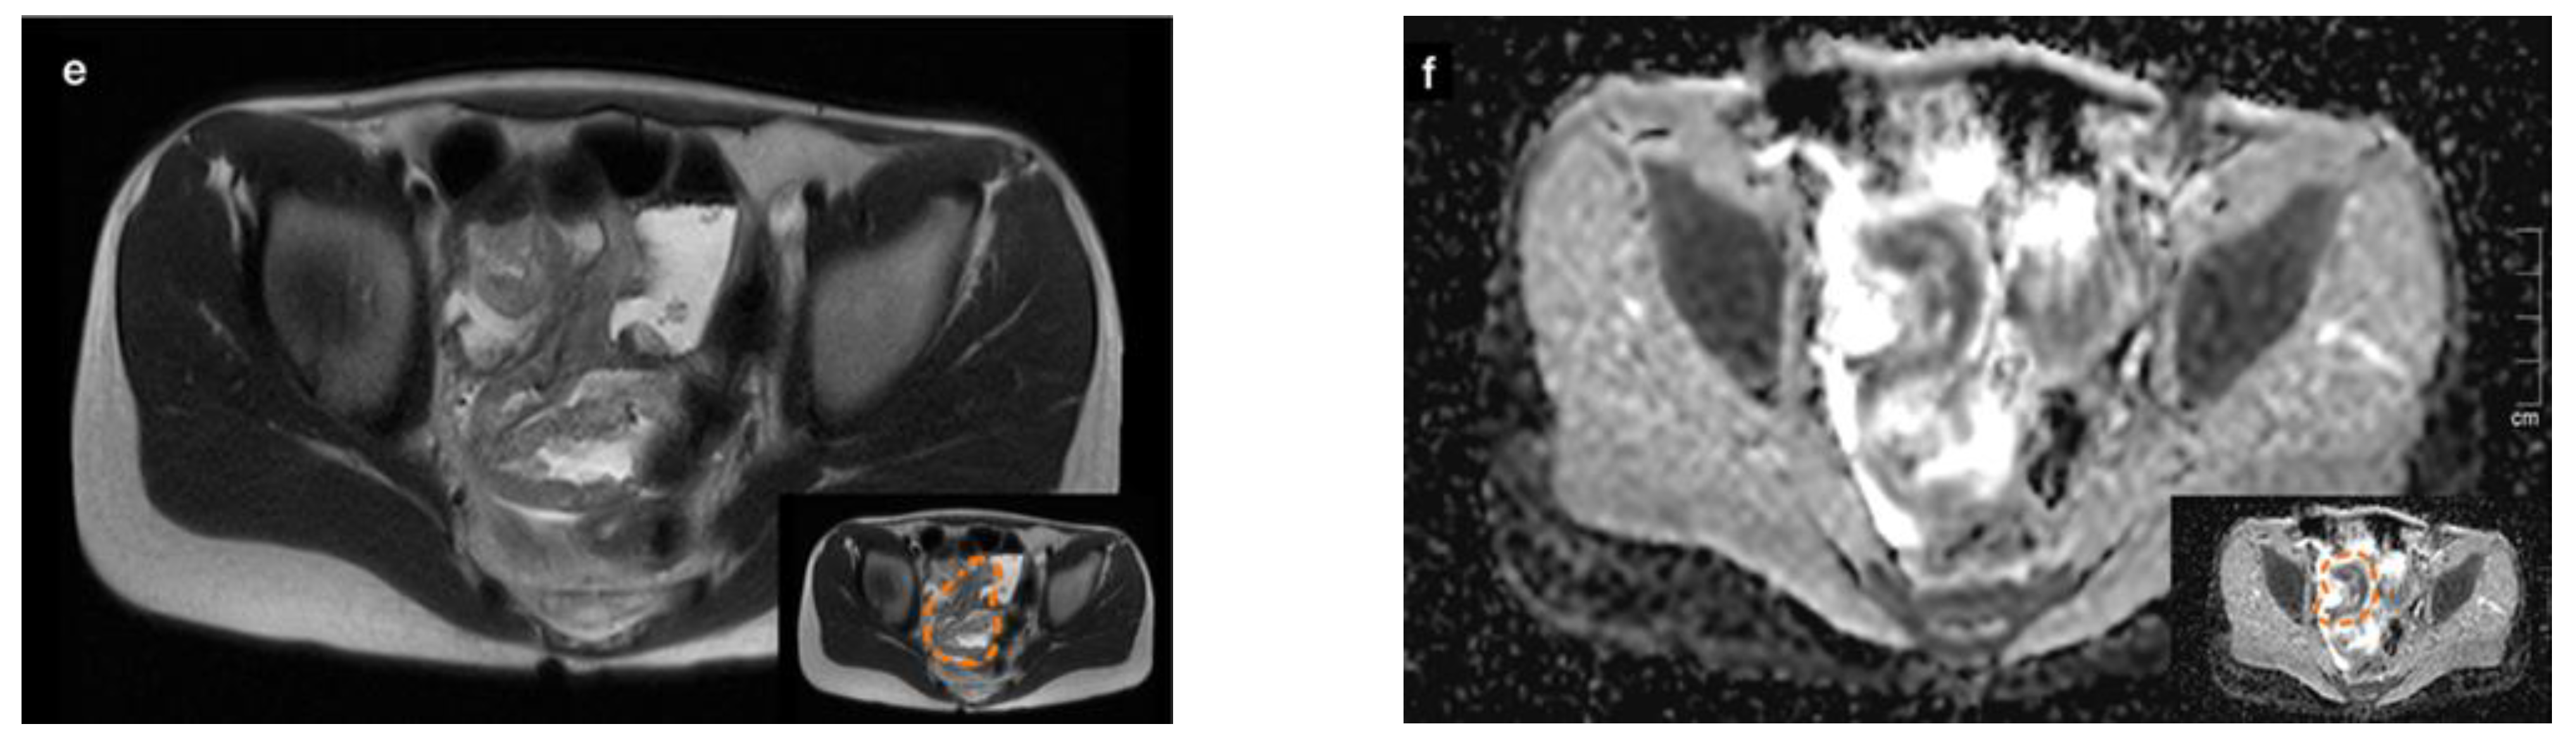

2. Case 1

2.3. Diagnostic Evaluation